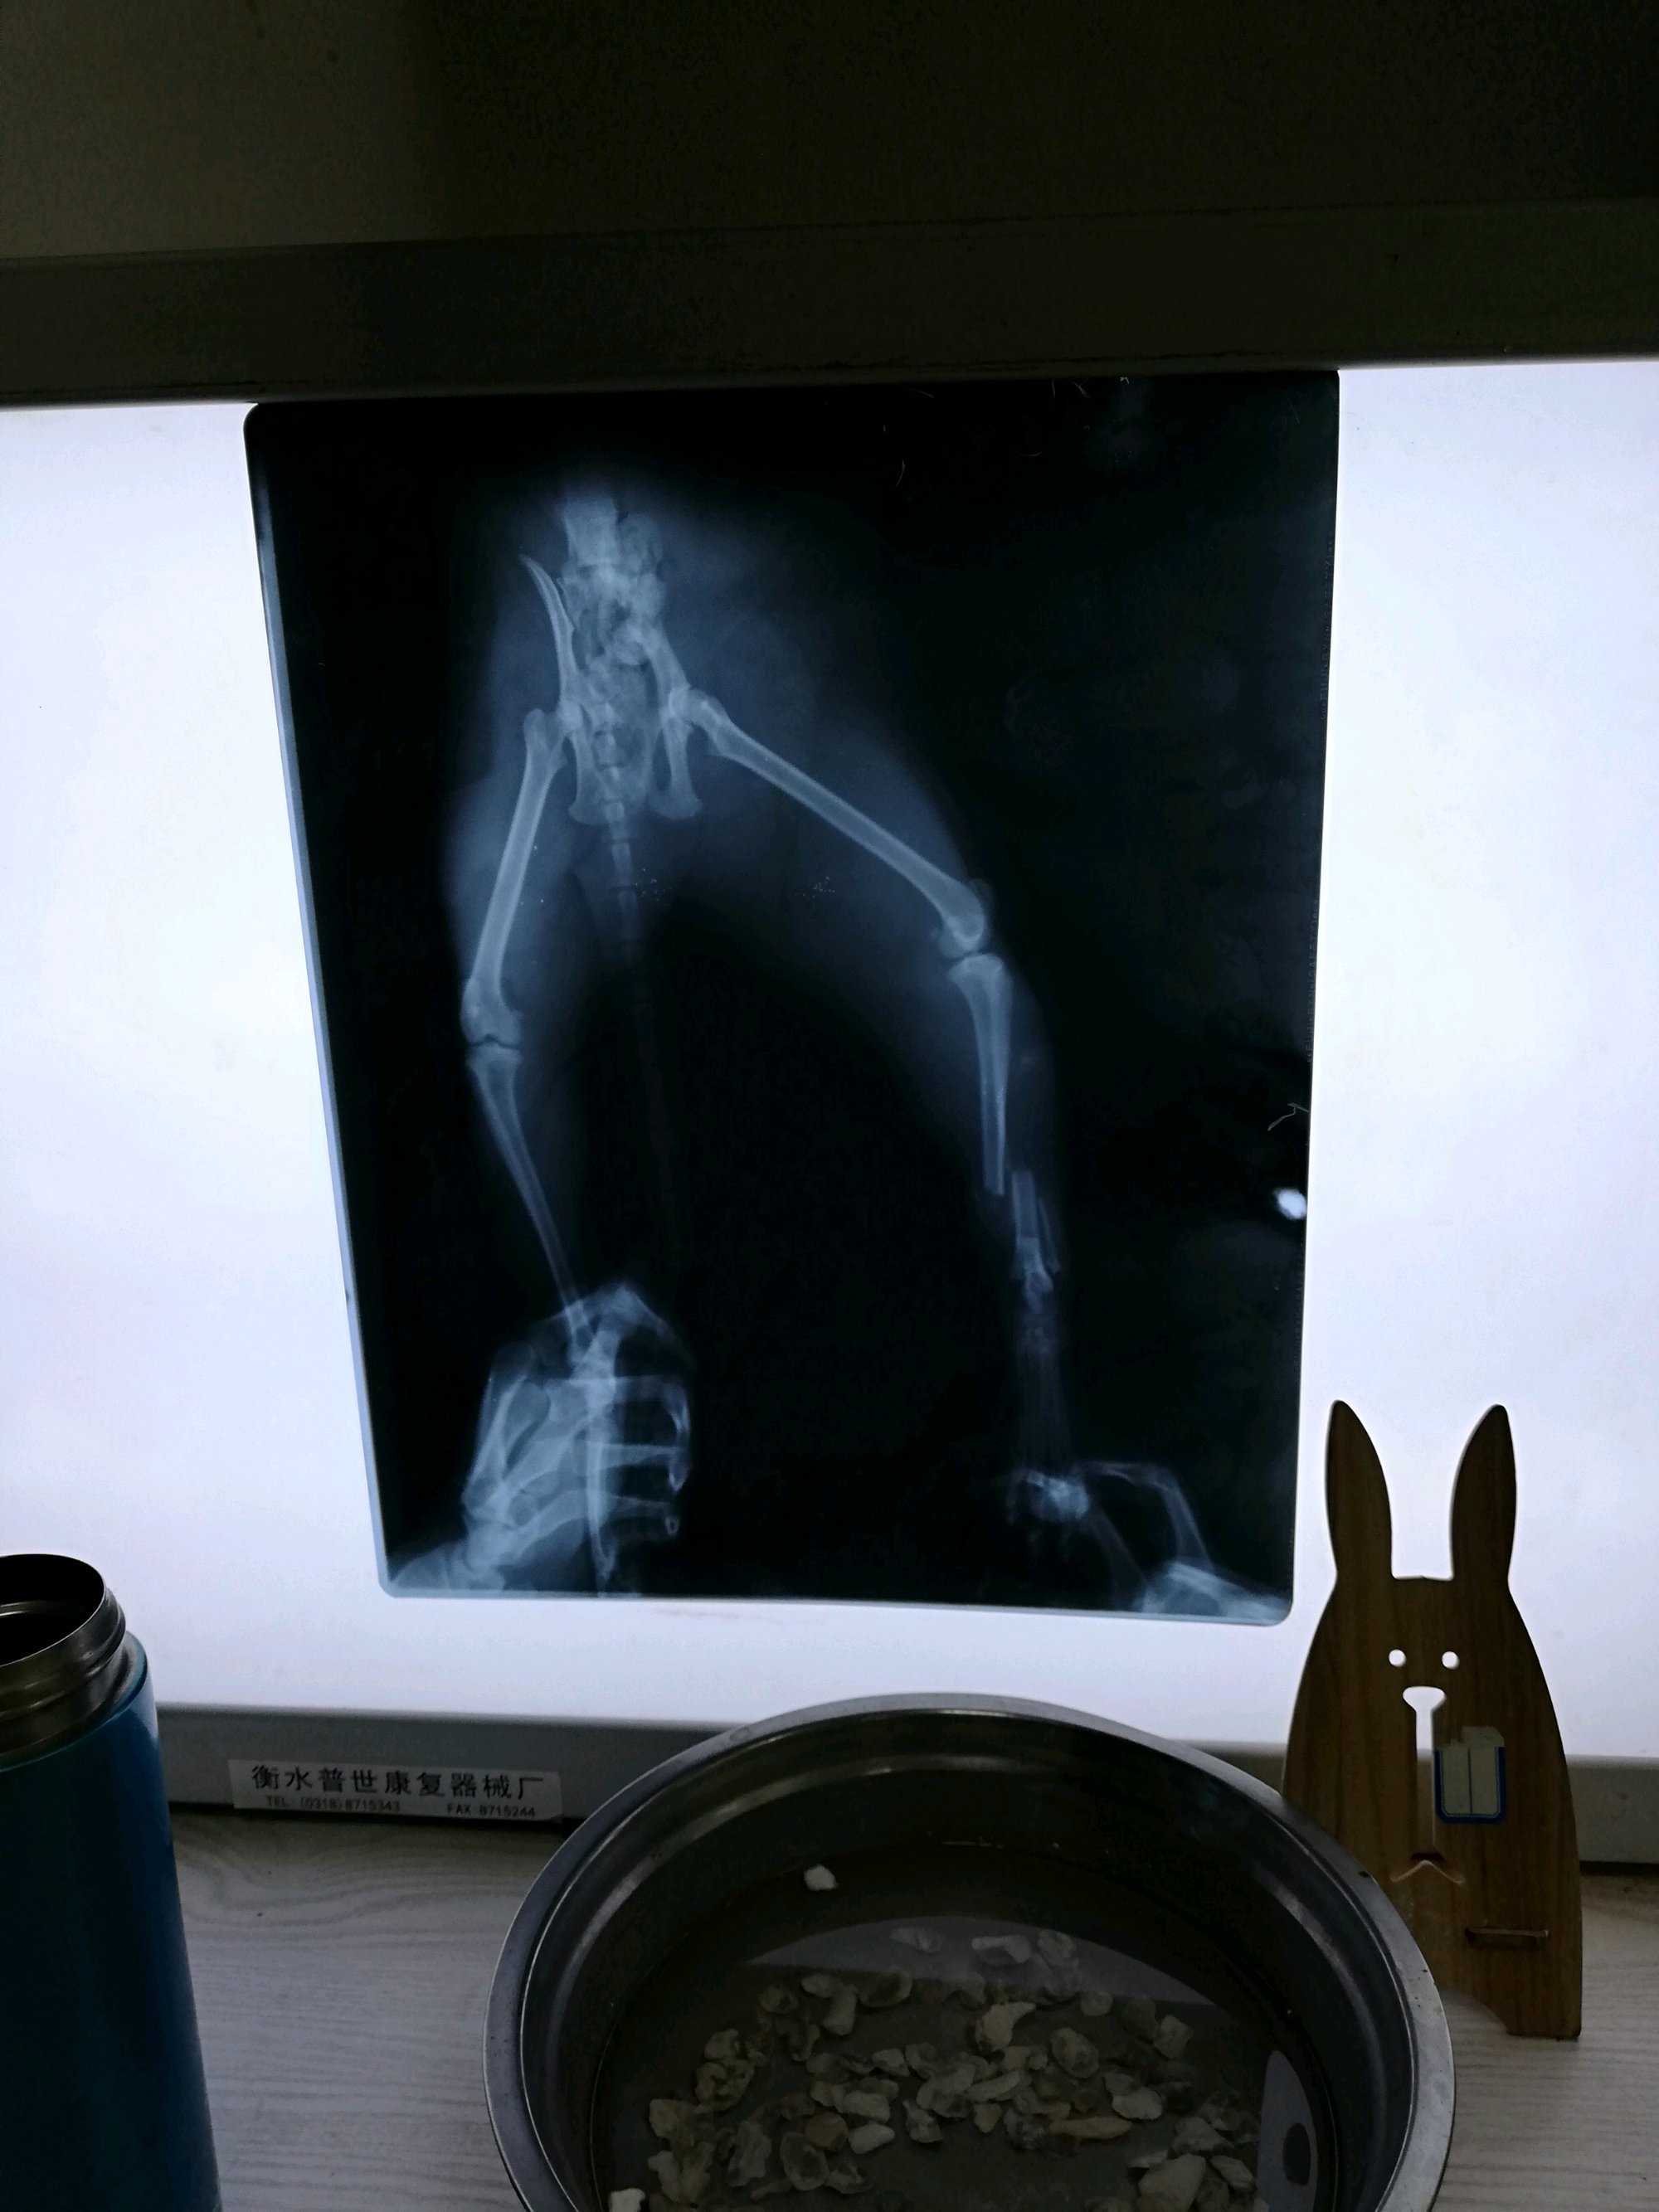

我家的喵子后腿骨折,一定要做内固定吗,做外固定医生只用硬纸片

我家的喵子后腿骨折,一定要做内固定吗,做外固定医生只用硬纸片,中药和绷带能治好吗,它有自愈的可能吗?